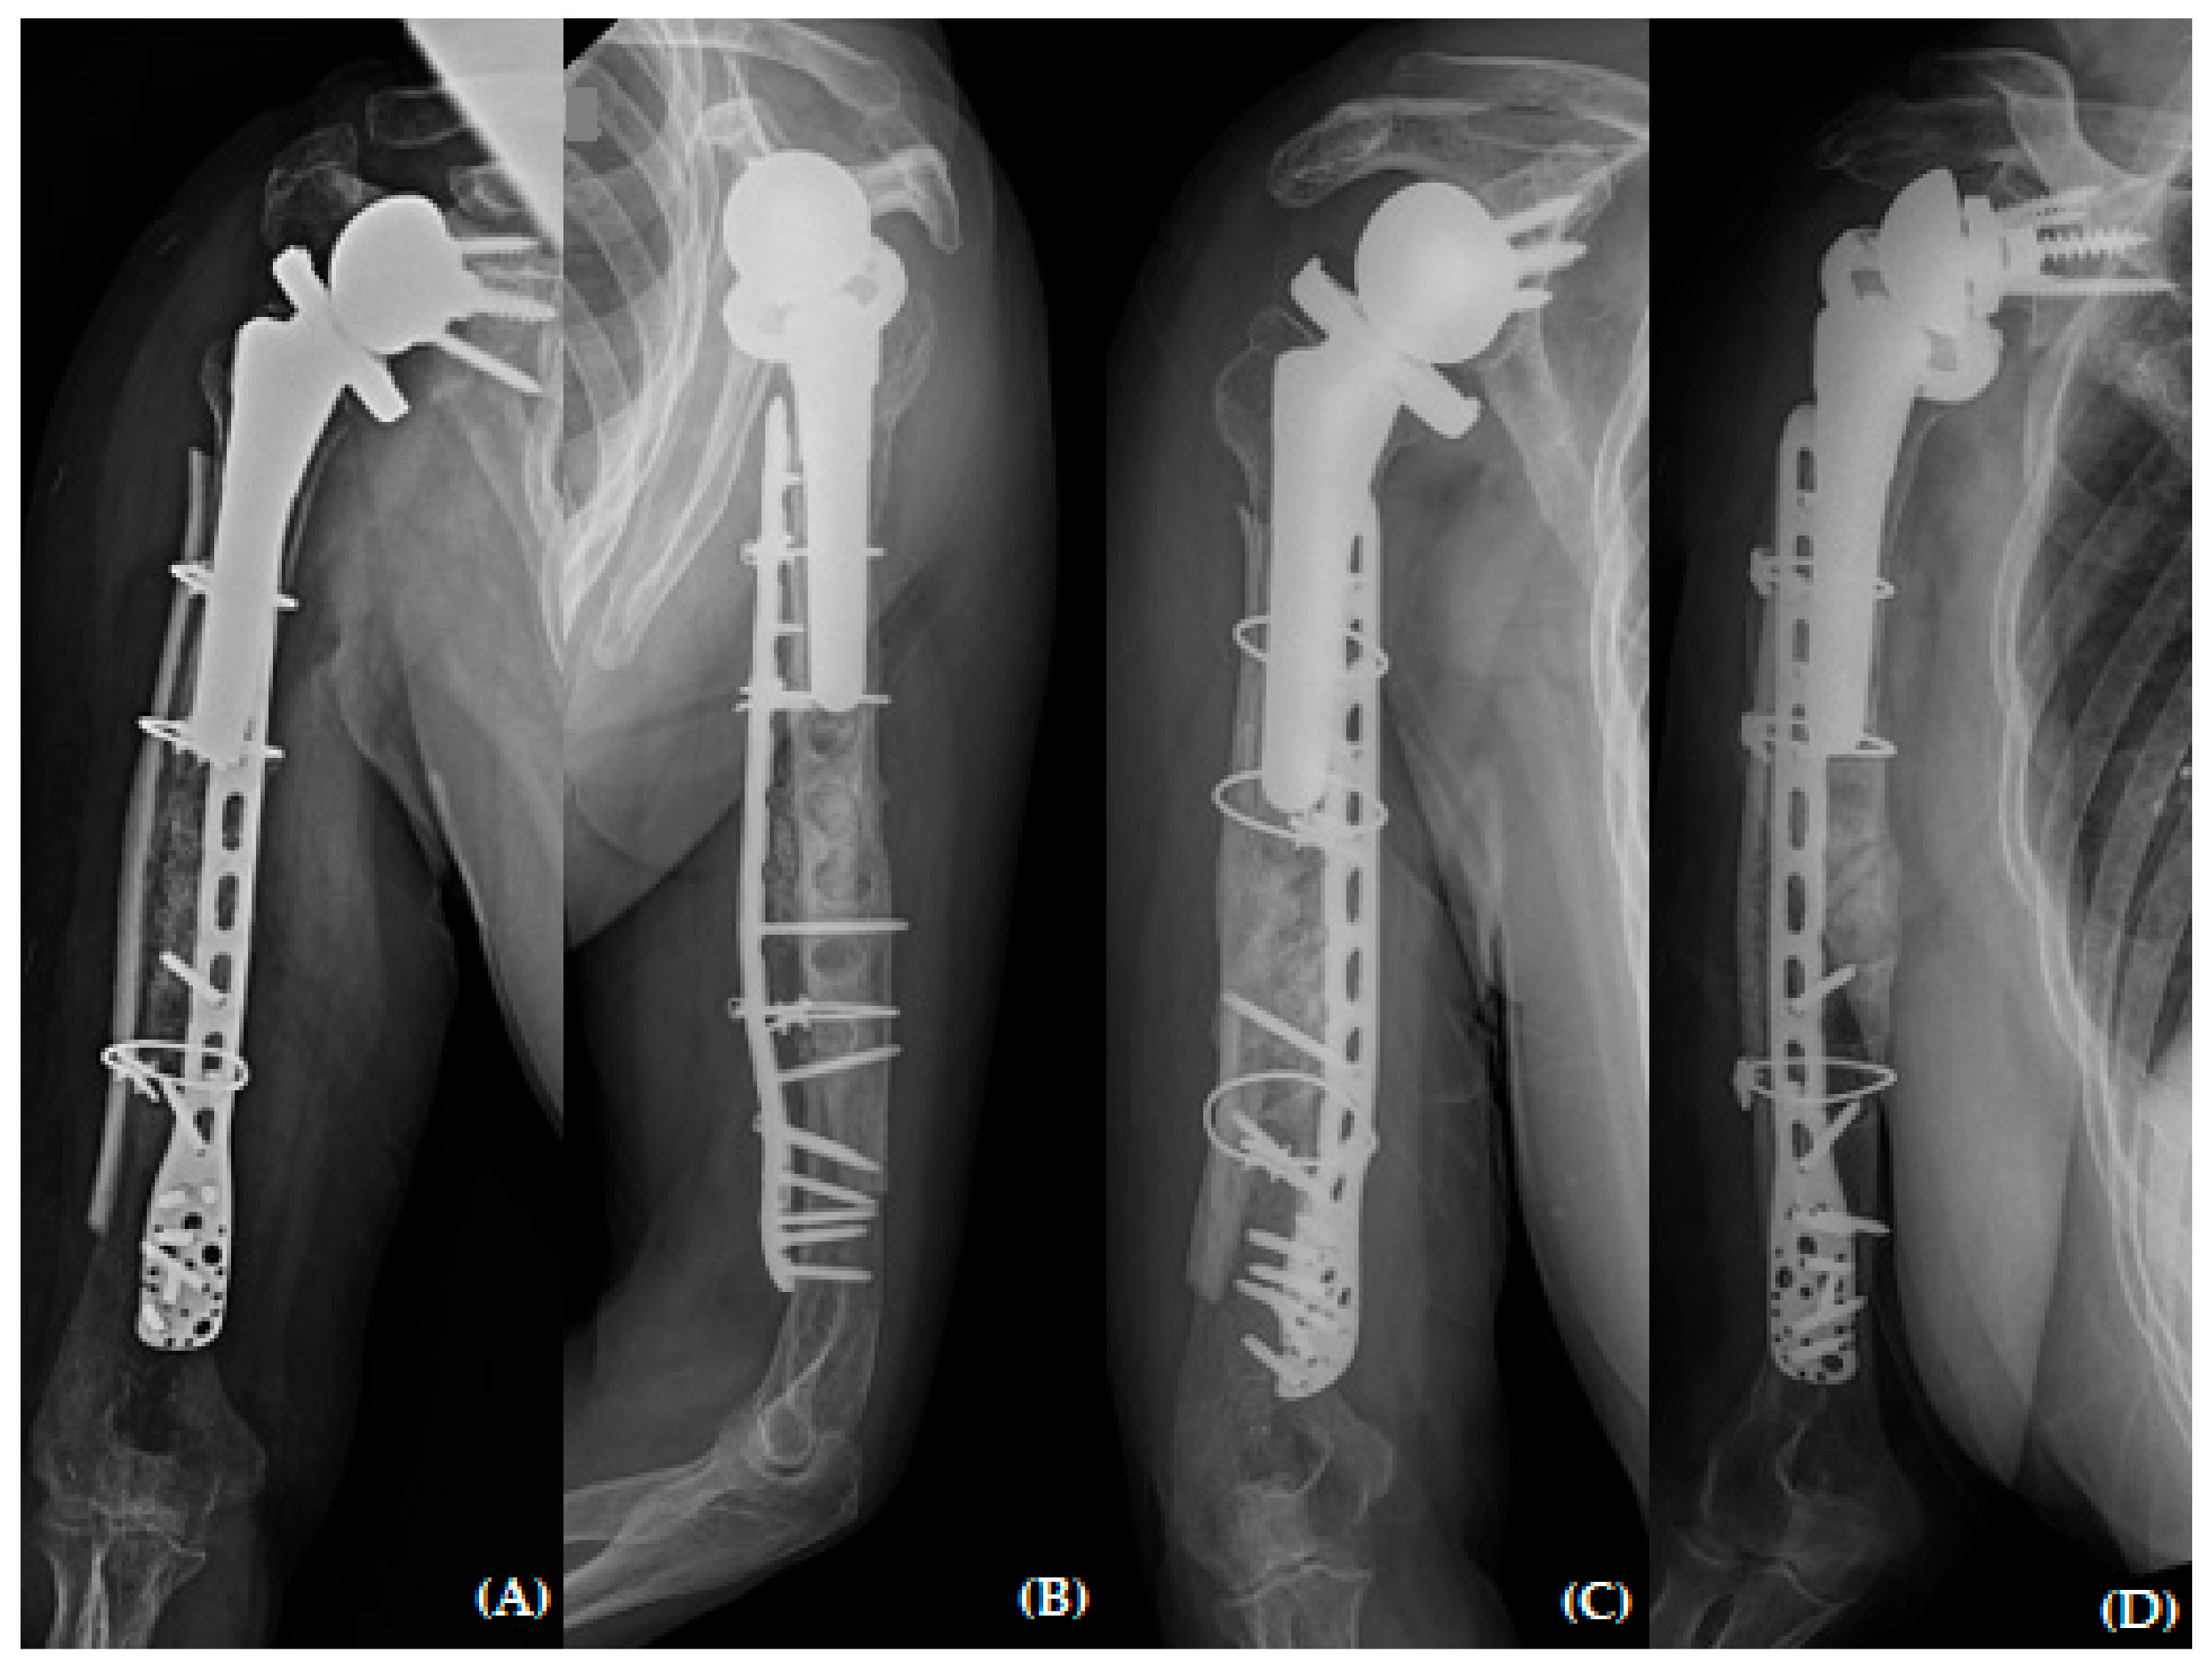

Figure 3. Plain radiographs of humerus (A) AP; (B) lateral views 3 months after open reduction and plate osteosynthesis for periprosthetic fracture.

Upon reviewing the simple radiographs captured 3 months after the operation, we observed breakage of the proximal wires; all screws had loosened without pulling out, callus formation was absent, and varus deformity was noticeable (Figure 3). The patient was treated conservatively with an abduction brace for 6 months post-operatively. On simple radiographs captured 6 months post-operatively, the fracture site displayed bone absorption and a noticeable progression of varus angulation (Figure 4). Radiographic findings confirmed atrophic non-union, necessitating a comprehensive approach to address both stability and maintain the structure of the anatomical biology through revision osteosynthesis. In order to discern the weakness reported by the patient, a cervical spine evaluation, electromyography (EMG), and nerve conduction velocity study (NCV) were conducted, and all results were confirmed to be within normal range.